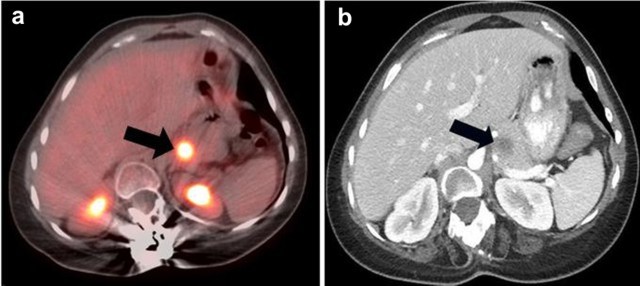

d) Lymphoma of the Pancreas

Lymphoma consists of Hodgkin lymphoma (15%) and non-Hodgkin lymphoma (85%). Together, they account for less than 10% of all cancers. Non-Hodgkin lymphoma is more aggressive than Hodgkin lymphoma, having a tendency for extra-nodal involvement. Non-Hodgkin lymphoma makes up of two subtypes: low-grade or aggressive non-Hodgkin lymphoma. Only Hodgkin lymphoma and aggressive non-Hodgkin lymphoma show a high affinity for FDG. An autopsy study showed that up to 30% of non-Hodgkin lymphomas metastasize to the pancreas [11]. Approximately 70% of pancreatic lymphomas respond well to chemotherapy [11]. Current evidence indicates that PET/CT is extremely useful in the staging and restaging of FDG-avid lymphomas (Figure 12). In addition, PET has a prognostic value in lymphoma treatment.

|

Figure 12. a. Fused axial PET/CT image shows a hypermetabolic lesion of non-Hodgkin lymphoma of the pancreas (arrow). The other two bright “spots? represent normal kidney excretion of FDG tracer. b. Corresponding axial CT image (arrow). |